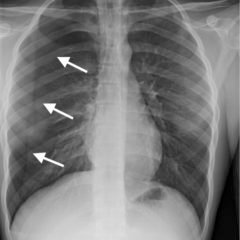

On physical examination, an 8-cm non-raised, erythematous lesion with central clearing was noted on the right posterior thorax. A small scab was located at the center of the lesion with no evidence of retained tick. No other rashes were present.

Lyme disease is a tick-borne illness caused primarily by the spirochete Borrelia burgdorferi. Ticks must be attached for a minimum of 48 hours in order to transmit the spirochete.1 Erythema migrans (EM) is the most common clinical manifestation of Lyme disease. EM is characterized by a slowly-expanding erythematous rash at the site of the tick bite, typically appearing between 7- and 14-days following tick attachment. Rashes range from 5cm to 30cm and may develop central clearing.2 Erythema migrans must be differentiated from initial erythema at the site of the bite due to a reaction to tick saliva. The differential includes southern tick-associated rash illness, erythema multiforme, cellulitis, contact dermatitis, and tinea corporis. The presence of erythema migrans has a sensitivity of 69% and a specificity of 98% for Lyme disease.3 Serological testing is not indicated in patients with EM, as only about 30% will be seropositive at presentation.4 Treatment of early Lyme disease consists of doxycycline preferentially, or amoxicillin, or cefuroxime for 14 days.6 Recurrence of erythema migrans after a full course of antibiotics is most likely due to re-infection rather than relapse.7 Prognosis is excellent with antibiotic treatment; however, those in endemic areas are at high risk for re-infection.8